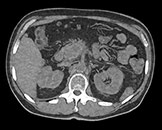

View an anatomical area using different spectral results.

Created by removing the iodine component from the image. Hounsfield Unit (HU) measurements from virtual non-contrast spectral results are comparable to true non-contrast scans for the majority of the organs, allowing VNC results to replace a true non-contrast scan.